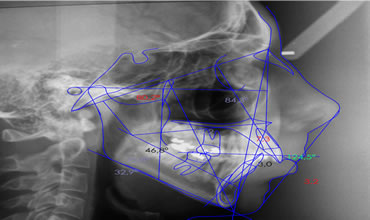

Análise Cefalométrica

Auxiliar no diagnóstico e controle dos tratamentos ortodônticos/cirúrgicos.